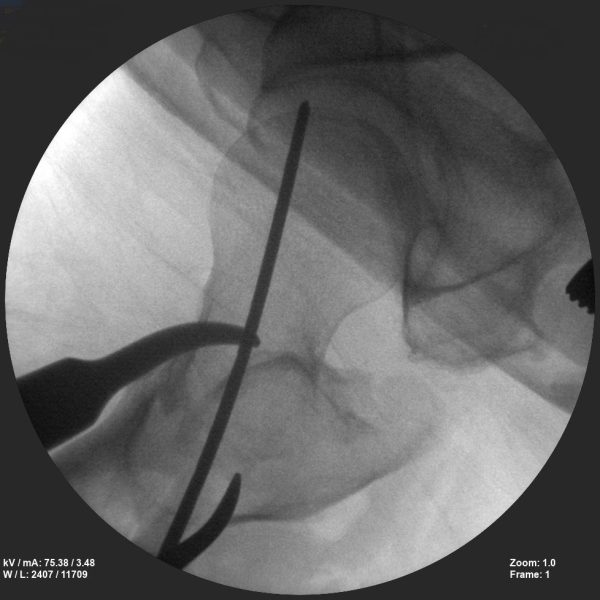

CRIF - Closed reduction internal fixation

ORIF - Open reduction internal fixation

Skan-C is a great C-arm for orthopaedic treatments for several reasons